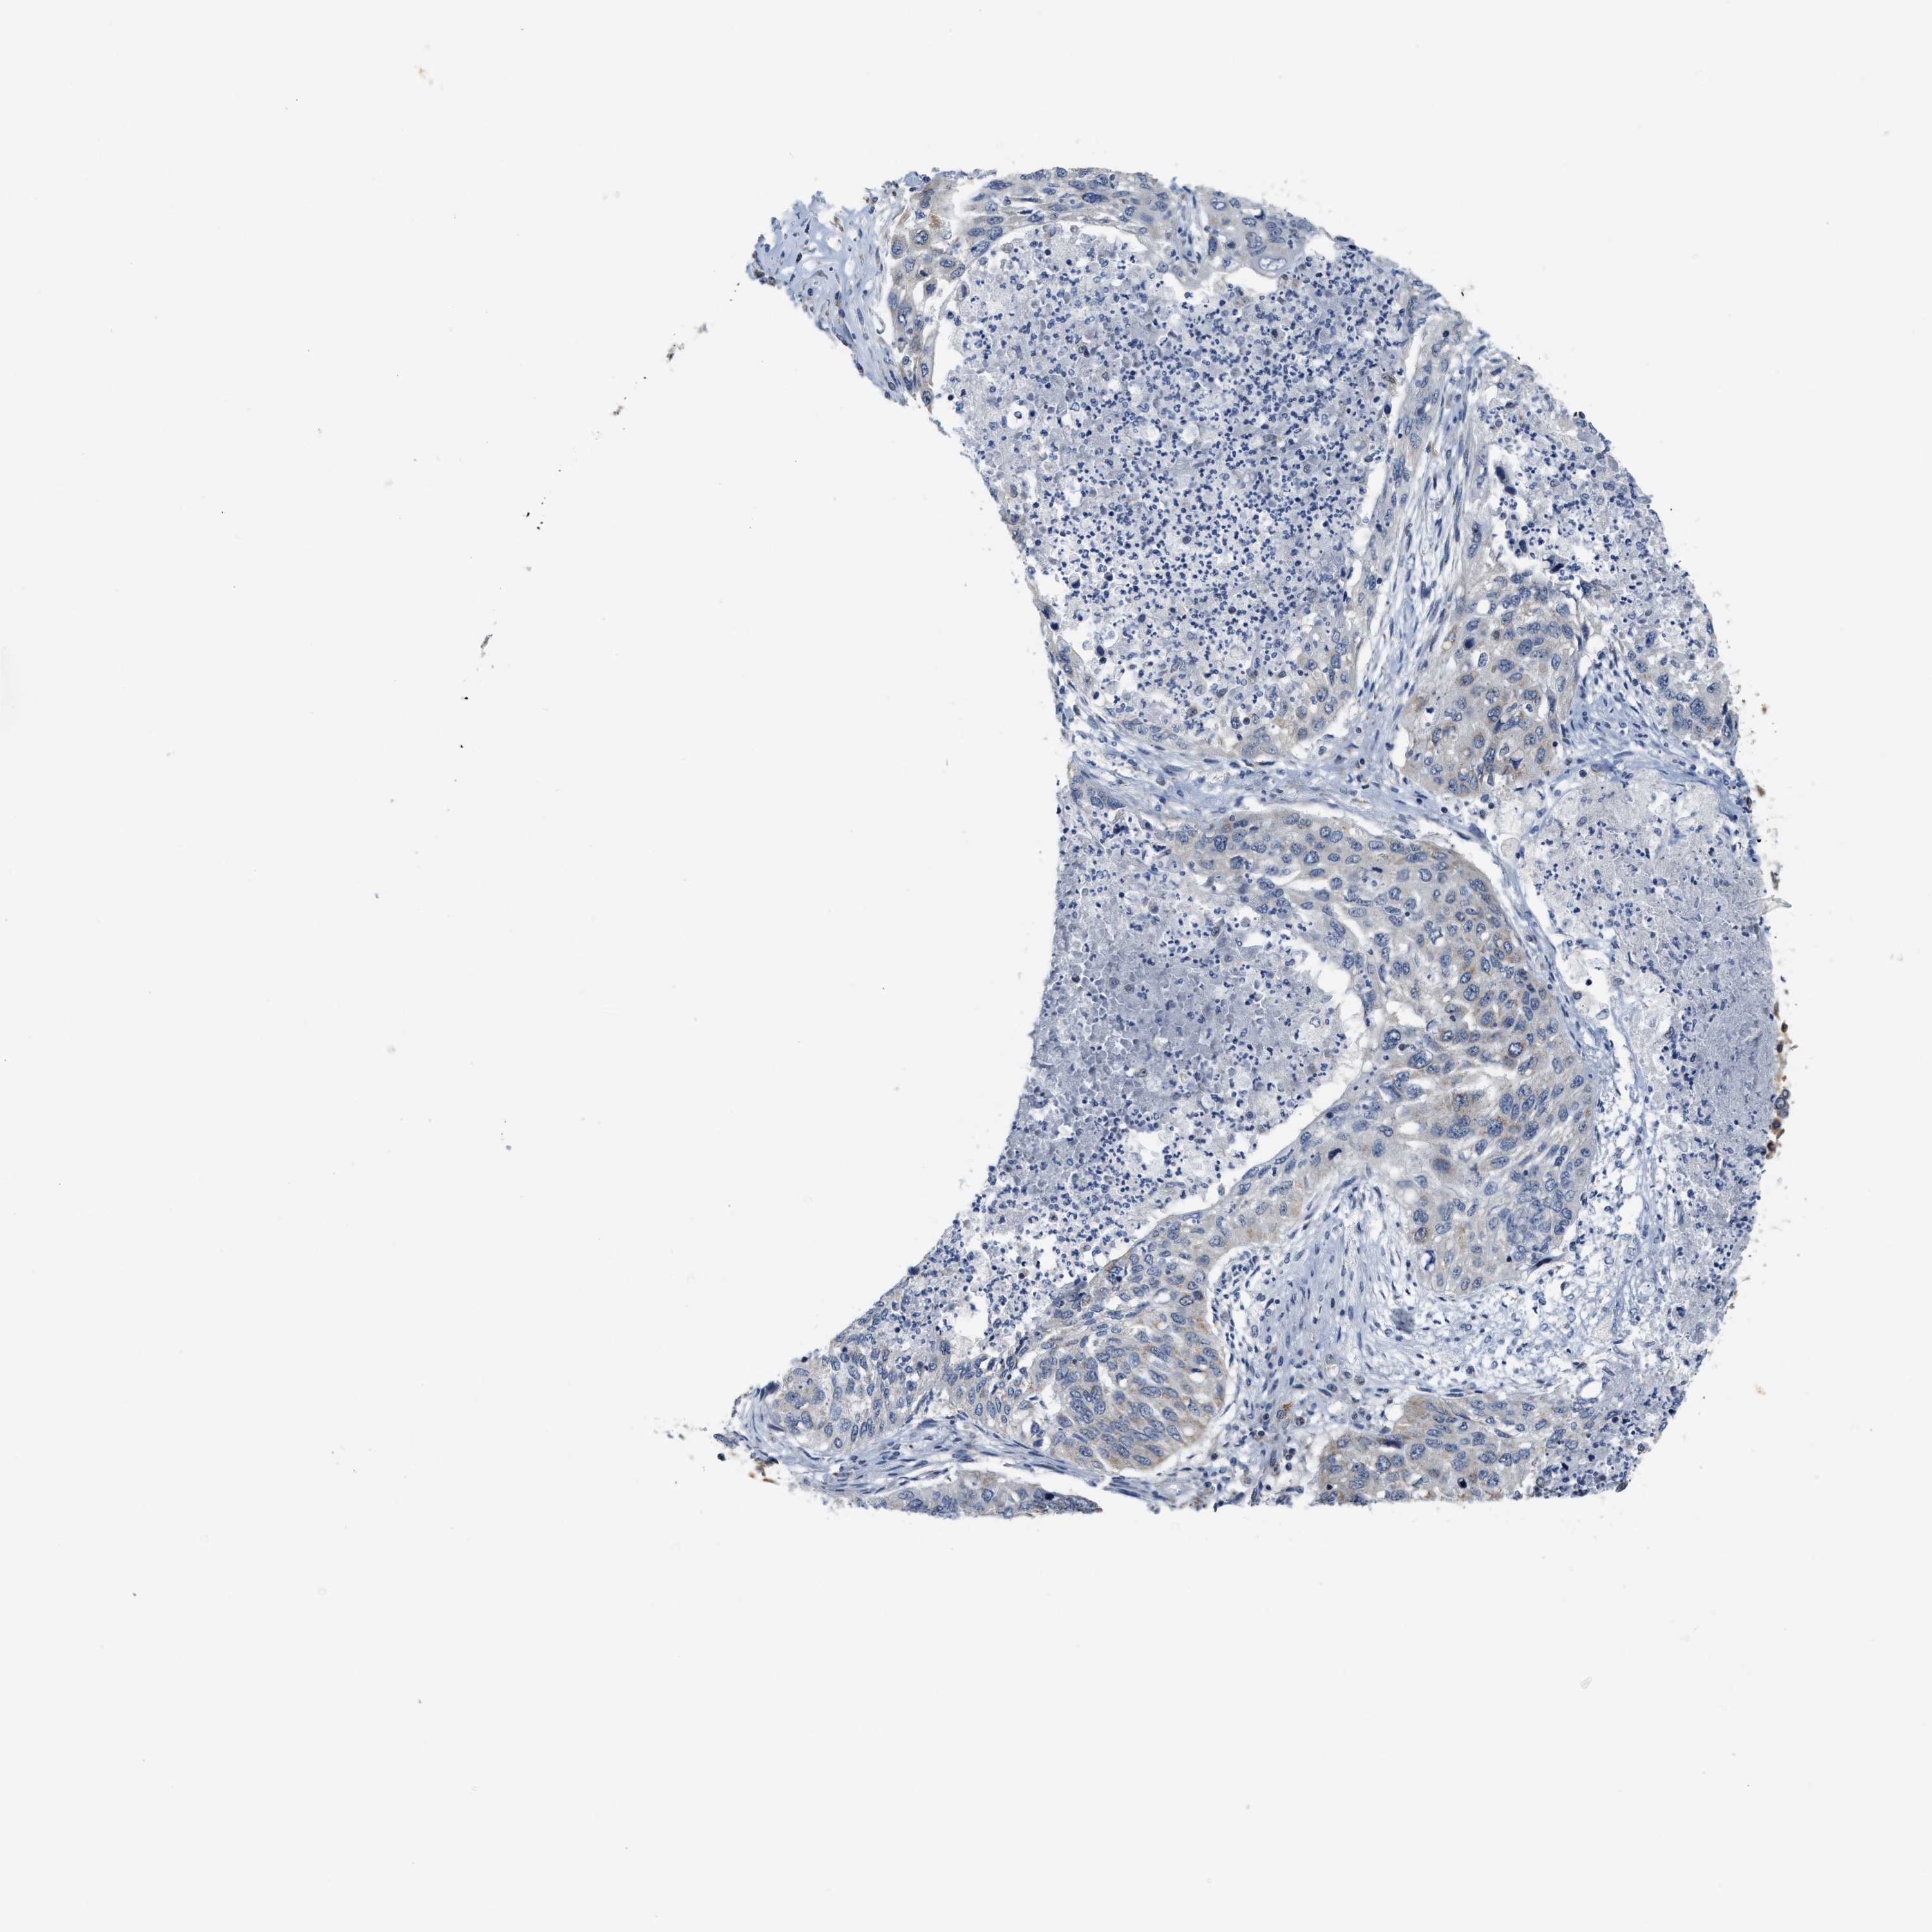

LUNG SQUAMOUS CELL CARCINOMA (TCGA) - Interactive survival scatter ploti

The Survival Scatter plot shows the clinical status (i.e. dead or alive) for all individuals in the patient cohort, based on the same data that underlies the corresponding Kaplan-Meier plots. Patients that are alive at last time for follow-up are shown in blue and patients who have died during the study are shown in red.

The x-axis shows the expression levels (FPKM) of the investigated gene in the tumor tissue at the time of diagnosis. The y-axis shows the follow-up time after diagnosis (years). Both axes are complimented with kernel density curves demonstrating the data density over the axes. The top density plot shows the expression levels (FPKM) distribution among dead (red) and alive patients (blue). The right density plot shows the data density of the survived years of dead patients with high and low expression levels respectively, stratified using the cutoff indicated by the vertical dashed line through the Survival Scatter plot. This cutoff is automatically defined based on the FPKM cutoff that minimizes the p-score. The cutoff can be changed by dragging the vertical line or by entering a cutoff value in the square labeled "Current cut-off".

Under the Survival Scatter plot the p-score landscape (black curve; left axis) is shown together with dead median separation (red curve; right axis). Dead median separation is the difference in median mRNA expression between patients who have died with high and low expression, respectively. It is calculated as follows: median FPKM expression of dead patients with high expression - median FPKM expression of dead patients with low expression. This is intended to aid the user in visually exploring custom cutoffs and the associated p-scores and dead median separation.

Individual patient data is displayed and can be filtered by clicking on one or more of the category buttons on the top of the page. Categories describing expression level and patient information include: high, low, alive, dead, female, male and tumor stages. The scale of the x-axis can be toggled between linear and log-scale by clicking on the "x log" button. Mouse-over function shows TCGA ID, patient information and mRNA expression (FPKM) for each patient.

& Survival analysisi

Kaplan-Meier plots summarize results from analysis of correlation between mRNA expression level and patient survival. Patients were divided based on level of expression into one of the two groups "low" (under cut off) or "high" (over cut off). X-axis shows time for survival (years) and y-axis shows the probability of survival, where 1.0 corresponds to 100 percent.

GIGYF1 is not prognostic in Lung Squamous Cell Carcinoma (TCGA)

: 10.58

Average pTPM 16.2

Number of samples 489